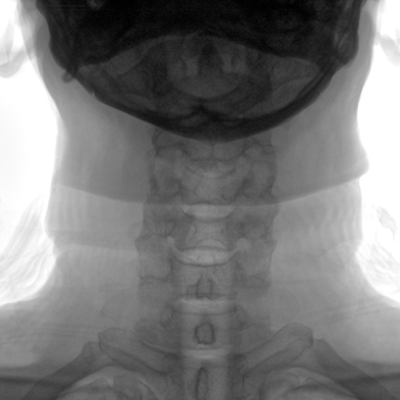

臨床適用科室:骨科、普通外科、矯形外科、創(chuàng)傷外科、泌尿外科、脊柱外科、疼痛外科、消化科、婦科等科室。

大尺寸動態(tài)平板探測器,高DQE、低噪聲、圖像清晰。采用多分辨率圖像增強(qiáng)處理技術(shù),不同部位不同圖像處理算法,滿足客戶多樣化的需求。

采用智能變頻脈沖透視技術(shù),優(yōu)化圖像質(zhì)量的同時降低輻射劑量,呵護(hù)醫(yī)患健康